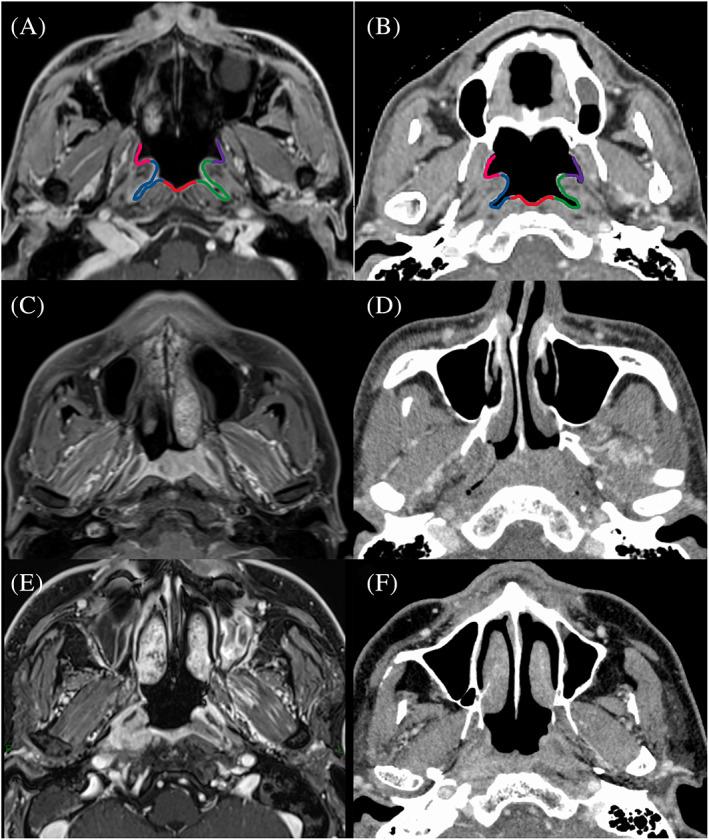

Between May 2009 and May 2019, 81 NPC patients who received definitive radiation therapy, in a hospital in Japan, were identified and the prognosis was investigated. p16, p53, and Epstein-Barr virus (EBV) status were assessed. Also, circumferential tumor extent in the nasopharyngeal cavity was assessed on a 5-point scale.

Nine and 72 patients were p16-positive and p16-negative, respectively. Fewer patients were EBV-encoded RNA in situ hybridization (EBER-ISH)-positive in the p16-positive group than in the p16-negative group ( < .01). Seventy-five patients were nonkeratinizing NPCs, and six patients were keratinizing NPCs. There were two p16-positive patients among the keratinizing NPCs.The mean circumferential tumor extent scores of 16-positive and p16-negative NPCs were 4.2 and 3.2, respectively with a statistically significant difference ( = .02). Two-year progression-free survival (PFS) of p16-positive and p16-negative patients undergoing chemoradiation therapy were 100% and 69%, respectively ( = .13).

In this study conducted in Japan, p16-positive NPC patients are minor but not very low, and the proportion of keratinizing NPCs was small. p16-positive NPCs were seen both in keratinizing and nonkeratinizing NPCs. P16-positive NPC had a tendency of better PFS than p16-negative NPC. This better prognosis might be due to the higher radiosensitivity of the p16-positive cell. Additionally, p16-positive NPCs seemed to spread more extensively in circumference along the nasopharyngeal mucosa than p16-negative NPCs.

材料与方法

p16阳性和p16阴性患者分别为9例和72例。p16阳性组中EBV编码RNA原位杂交(EBER-ISH)阳性的患者少于p16阴性组(<0.01)。75例患者为非角化型NPC,6例患者为角化型NPC。在角化型NPC中有2例p16阳性患者。p16阳性和p16阴性NPC的平均周向肿瘤范围评分分别为4.2和3.2,差异有统计学意义(=0.02)。接受放化疗的p16阳性和p16阴性患者的两年无进展生存率(PFS)分别为100%和69%(=0.13)。

在日本进行的这项研究中,p16阳性NPC患者占少数但并非极低,角化型NPC的比例较小。在角化型和非角化型NPC中均可见p16阳性NPC。与p16阴性NPC相比,p16阳性NPC有更好的PFS趋势。这种较好的预后可能是由于p16阳性细胞具有更高的放射敏感性。此外,与p16阴性NPC相比,p16阳性NPC似乎在鼻咽黏膜周围扩散得更广泛。